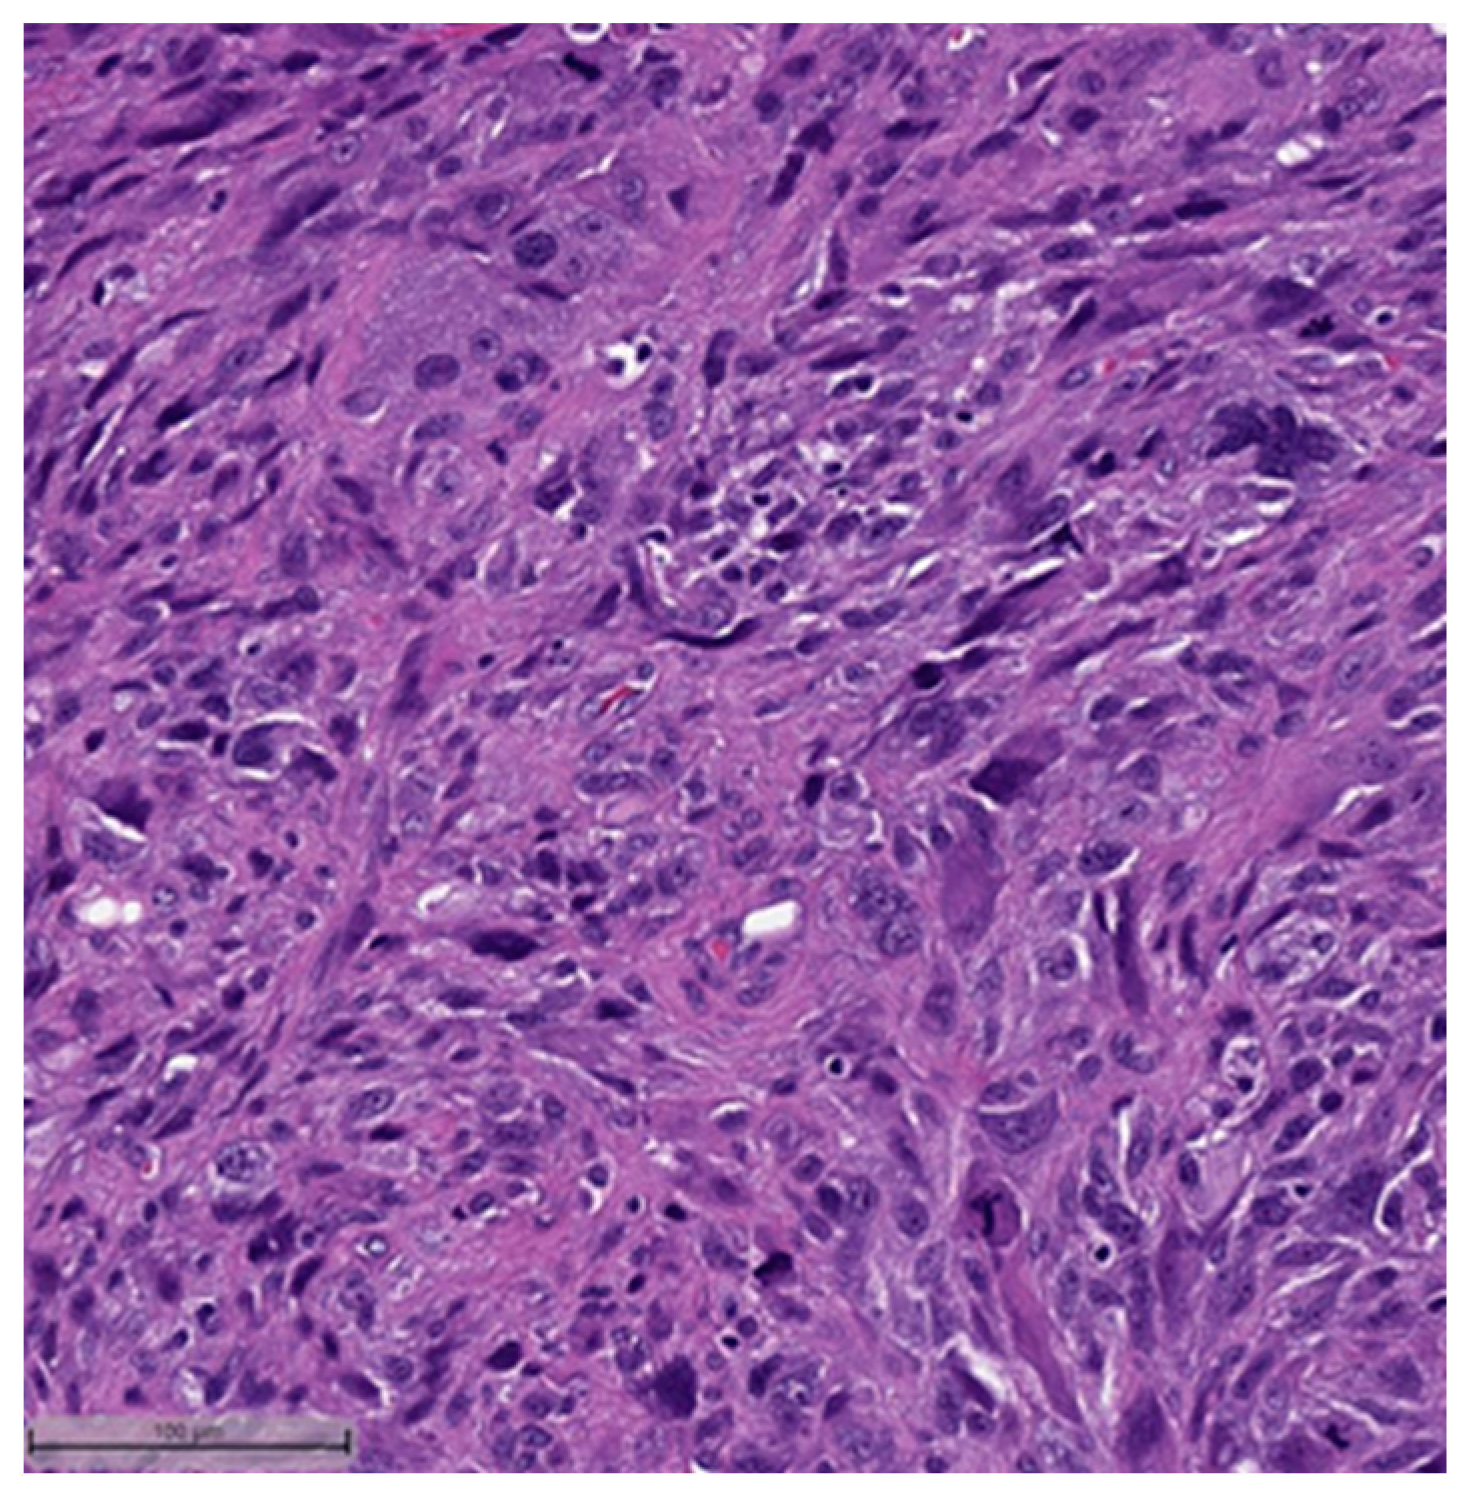

Figure 7.

Metaplastic breast carcinoma with osseous differentiation (H&E, 20×).